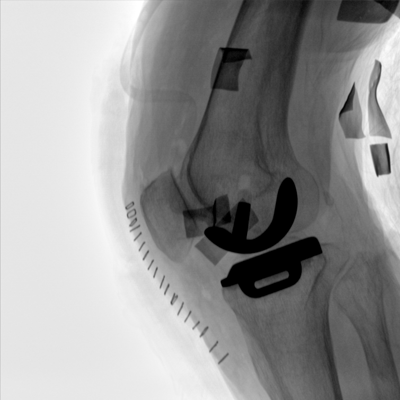

大尺寸動態(tài)平板探測器,高DQE、低噪聲、圖像清晰。采用多分辨率圖像增強(qiáng)處理技術(shù),不同部位不同圖像處理算法,滿足客戶多樣化的需求。

圖形化操控界面設(shè)計:設(shè)有多種人體特征攝影參數(shù),操作簡便。雙向紅光十字定位系統(tǒng):實現(xiàn)無射線下的高效定位。信息共享:遵循DICOM3.0格式接口,可無縫對接云PACS系統(tǒng)。

多角度自由旋轉(zhuǎn),滿足患者復(fù)雜擺位需求。